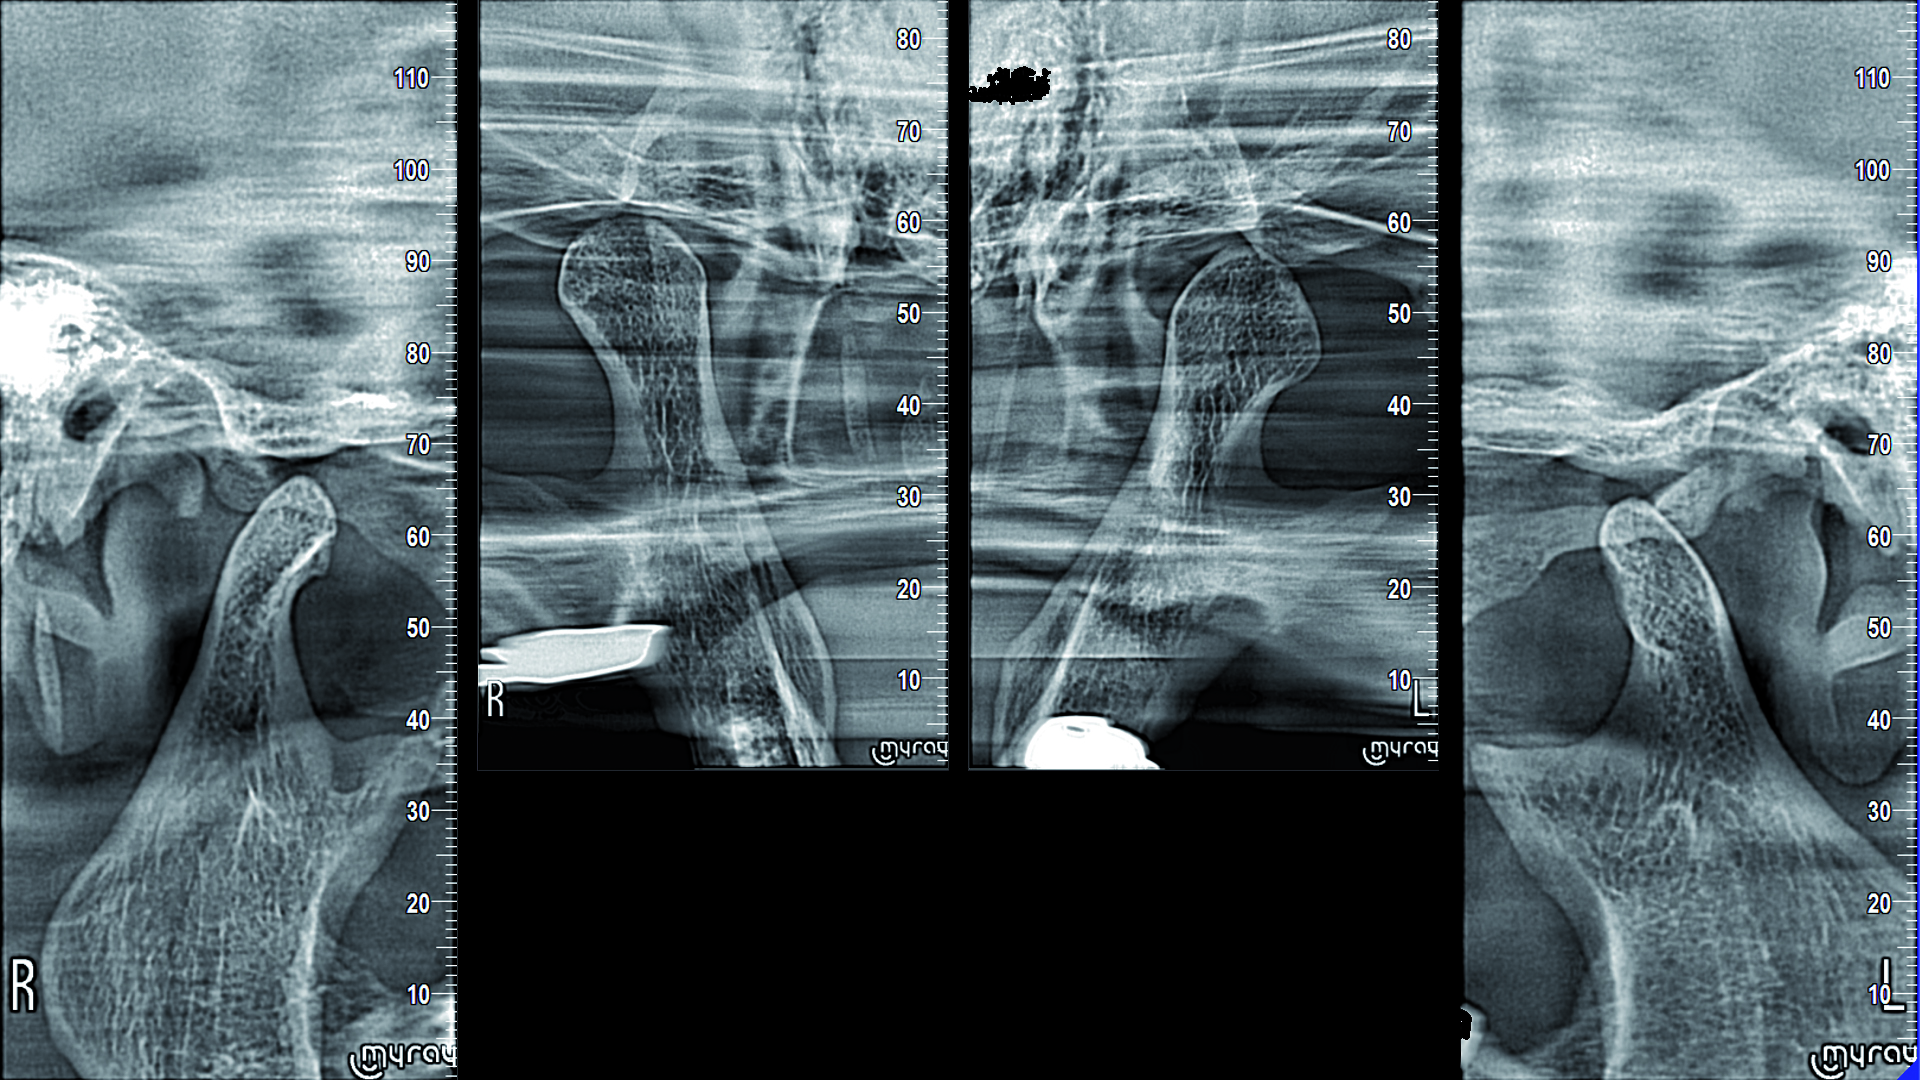

Yeni nesil hassas Cmos Flat Panel Teknolojisi. Görüntü kesitleri eskiye göre 2 kat daha keskin ve net görüntü almayı sağlamaktadır. Panoramik görüntülemede devrim yaratan Panoral 5 MultiPan çekim tekniği ile tek panoramik doz ile 5 ayrı katmanda görüntü alınır. Reel 16 bit yüksek gri skalası ile yüksek çözünürlük ve kesin tanı imkânı sunmaktadır. PANORAL 5 MULTIPAN Panoramik Röntgen Çekim Tekniği: CMOS Flat Panel Hassas Sensör teknolojisi tek bir panoramik doz ile horizontal düzlemde 3 mm. aralıkla, hastanın 5 ayrı vertikal panoramik görüntüsünün elde edilmesini sağlamaktadır. Bu şekilde net alan derinliğine girmeyen bir diş var ise bir önceki veya bir sonraki filmde görülebilir. Panoral 5 MULTIPAN görüntüleme tekniği; maloklüzyon ve hasta pozisyonlandırma hataları nedeniyle oluşabilecek görüntü bozukluklarını elemine edebilmektedir. Böylelikle panoramik röntgen çekimlerinde pozisyonlandırma hatalarına bağlı çekim tekrarlarına da gerek kalmaz.

• Maksimum çözünürlük ve ortogonalite • Sabit büyütme • Ark segmentasyonu

• Ağız açık veya kapalı PA ve LL projeksiyon • Tek veya çift tarama • Çok açılı inceleme (x3)